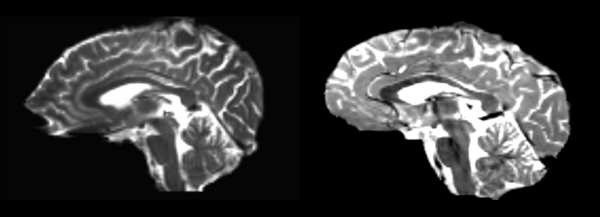

Linear

- 53-t2 -> 31-t1 = lin1

- lin1 -> 53-t2 = lin2

The image shows lin2 and 53-t2 side by side. The image shows there appears to be some change beyond loss of detail, possibly a L-R shift in the front.